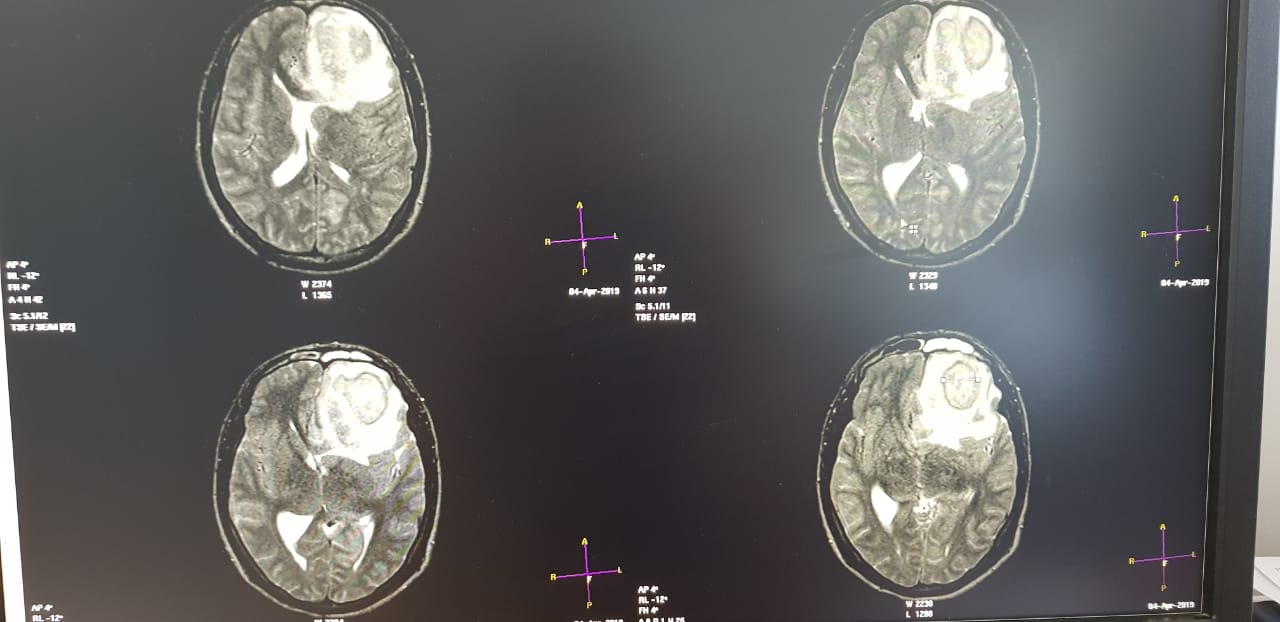

Пациент поступил в бессознательном состоянии в Мангистаускую областную больницу (МОБ) 4 апреля. У него было обнаружено гнойное образование в голове. Об этом сообщили в пресс-службе управления здравоохранения Мангистауской области.

Нейрохирург после обследования пациента обнаружил у него гнойник в головном мозге. В ходе операции, длившейся более четырех часов, объемное гнойное образование было удалено.

- После успешного удаления абсцесса состояние больного остается крайне тяжелым, но стабильным. Со слов родственников и сопровождающих, пациент около двух месяцев назад на родине получил травму головы в быту, - сообщили в пресс-службе управления здравоохранения.